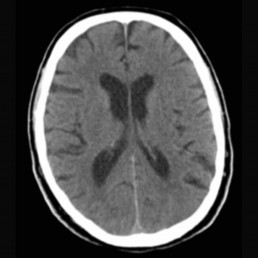

Many aneurysms are diagnosed when they bleed. Most aneurysms are located on arteries that surround the brain in a compartment called the subarchnoid space. When these aneurysms rupture the bleeding is around the brain, called a subarchnoid haemorrhage. The classical symptom is a sudden agonizing headache, sometimes with a transient loss of consciousness. The diagnosis of an aneurysmal subarachnoid haemorrhage is made by a CT scan.

Normal CT head: